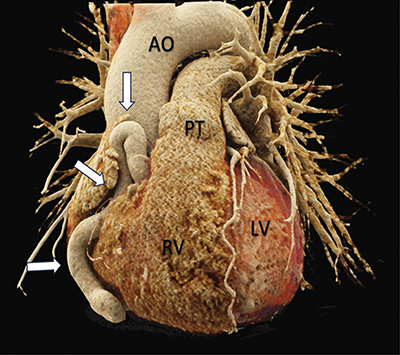

Figure 1

3D rendered cardiac CT-angiography reveals a tortuous dilation of the right coronary artery (white arrows). Front view.

Source: AO = Aorta, PT = Pulmonary Trunk, RV = Right ventricle, LV = Left Ventricle.